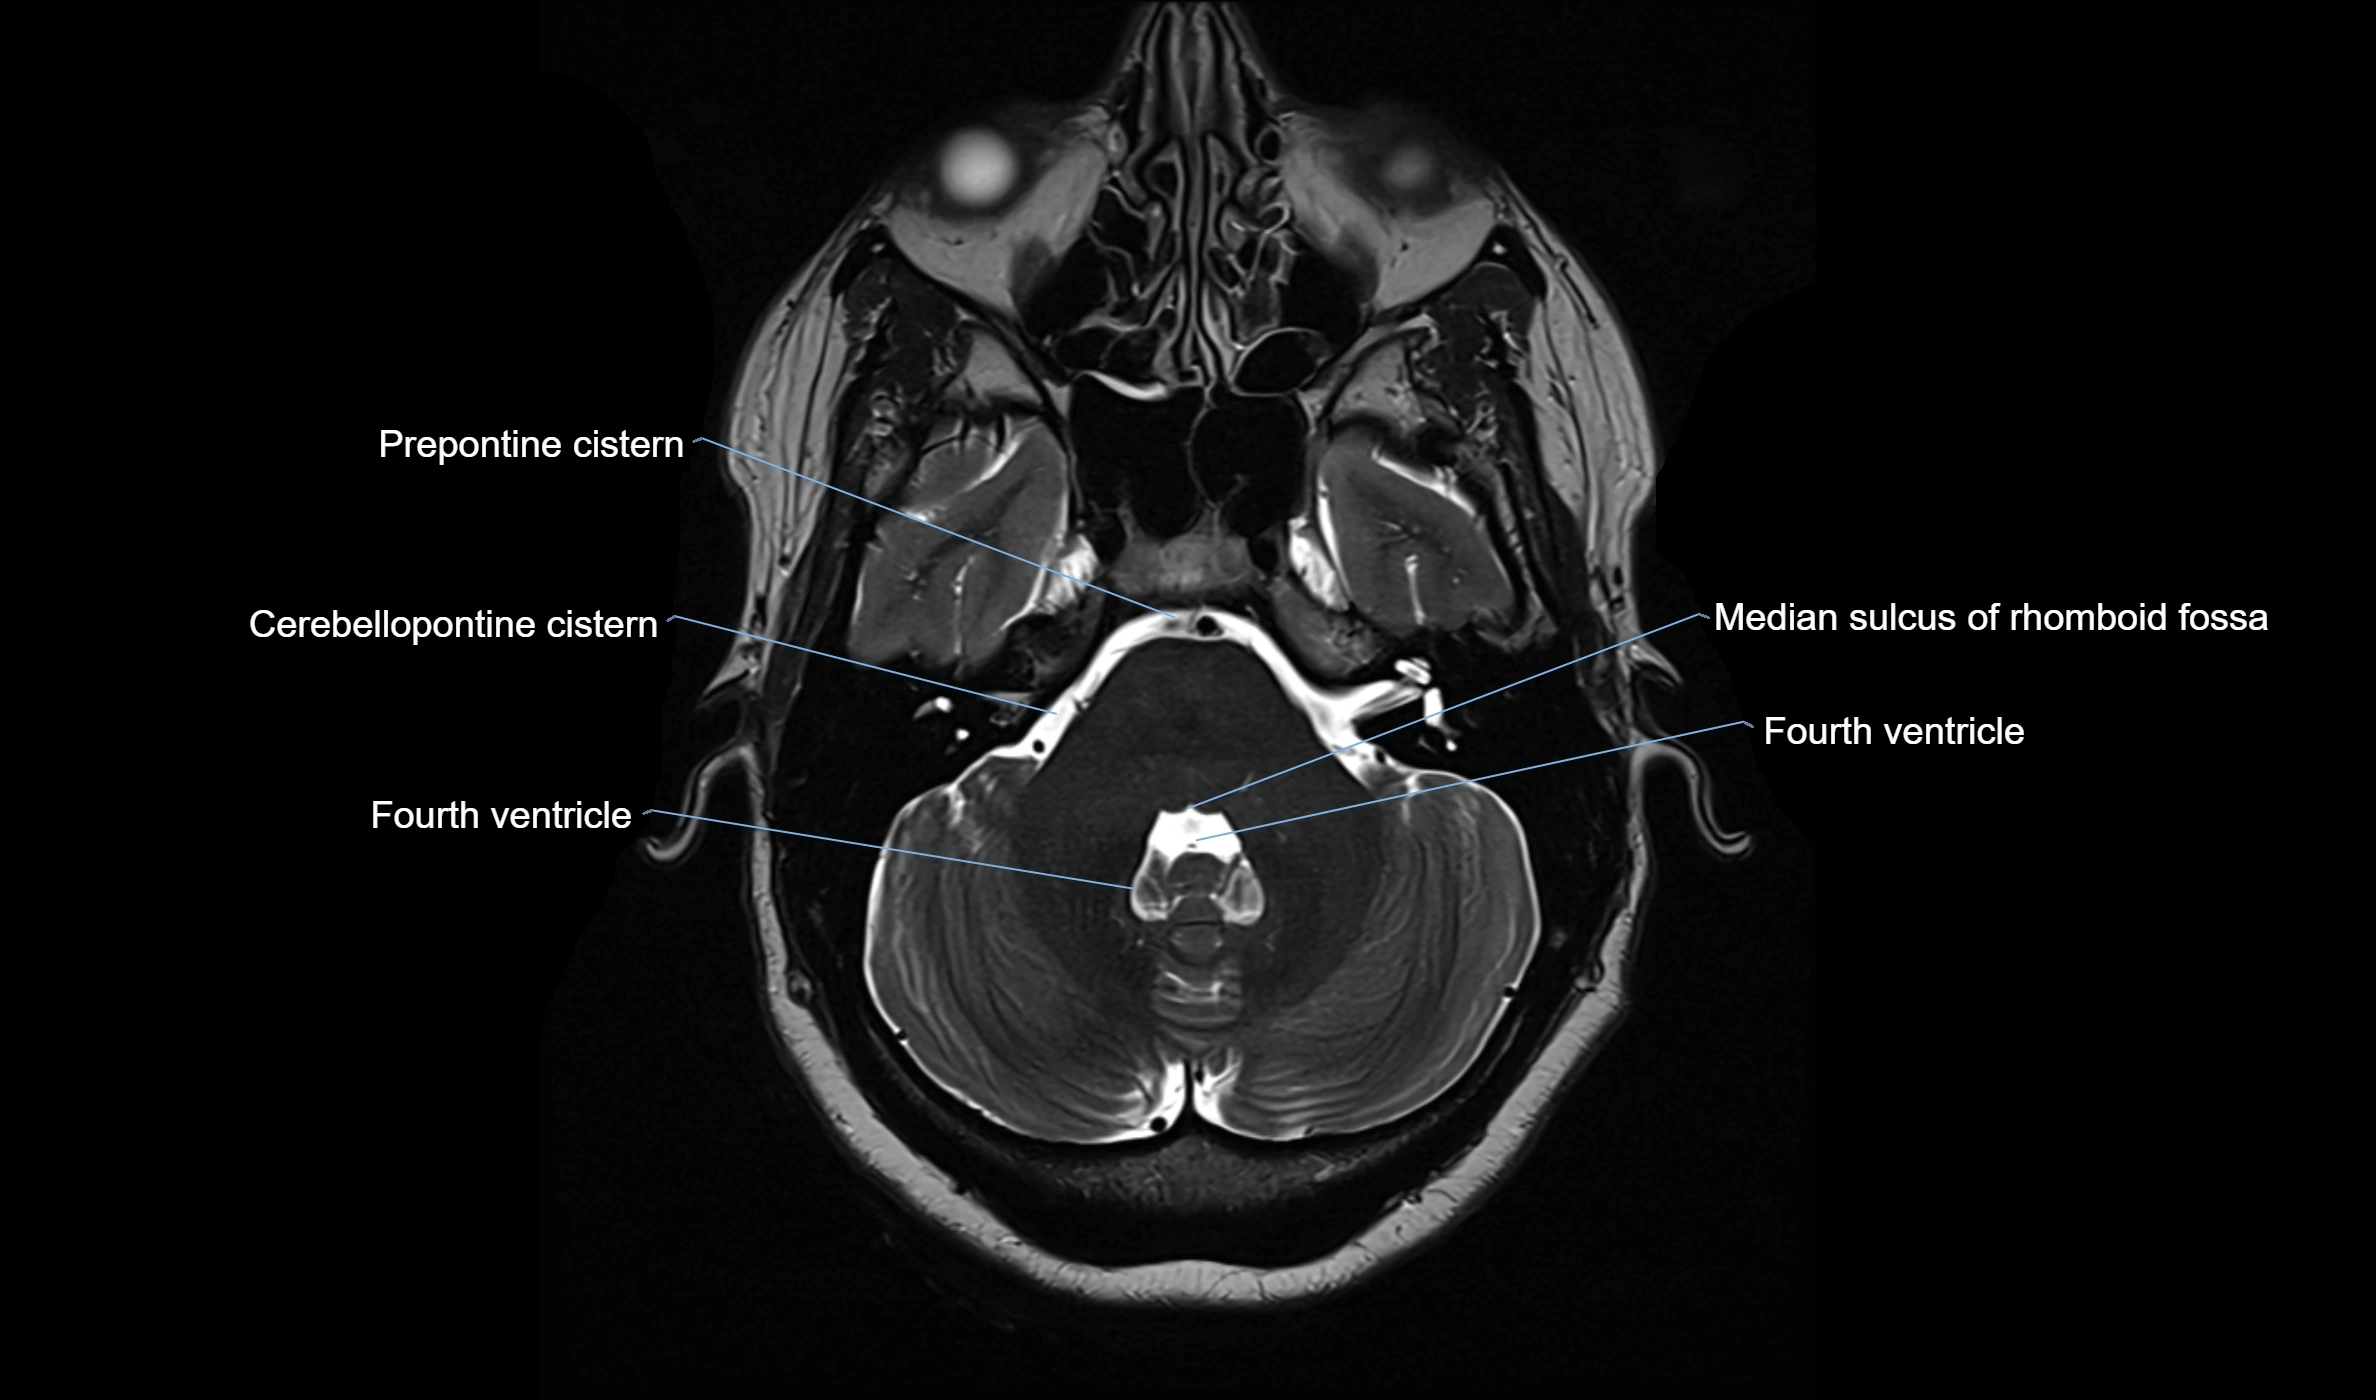

MRI images

image